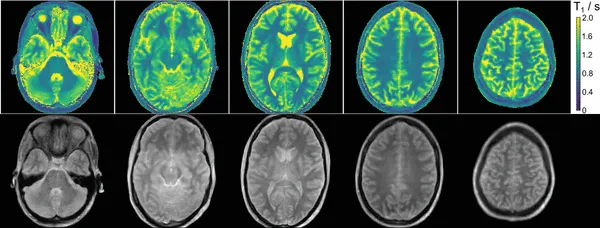

Simultaneous multi-slice T1 mapping in seconds

Ten brain MRI images

We designed a radial simultaneous multi-slice (SMS) acquisition with inversion preparation and nonlinear model-based reconstruction to achieve multi-slice T1 mapping within ~4 seconds. This approach offers dramatic acceleration while maintaining quantitative accuracy, facilitating rapid multiparametric studies.

Wang X, et al., Magnetic Resonance in Medicine, 2021; 85: 1258 - 1271. [Open Access, Code, Data].